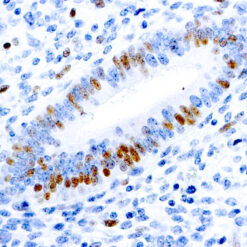

Synaptophysin (SYP02)

This antibody isspecific to a 38 kDa protein. Synaptophysin is an glycoprotein occurring in presynaptic vesicles of neurons in the brain, spinal cord, retina, vesicles of adrenal medulla and in neuromuscular junctions. This antibody reacts with neuroendocrine neoplasms of neural as well as epithelial types.

| Clone | SYP02 |

| Cellular Localization | Cytoplasmic |

| Positive Control Tissue | Pancreas |